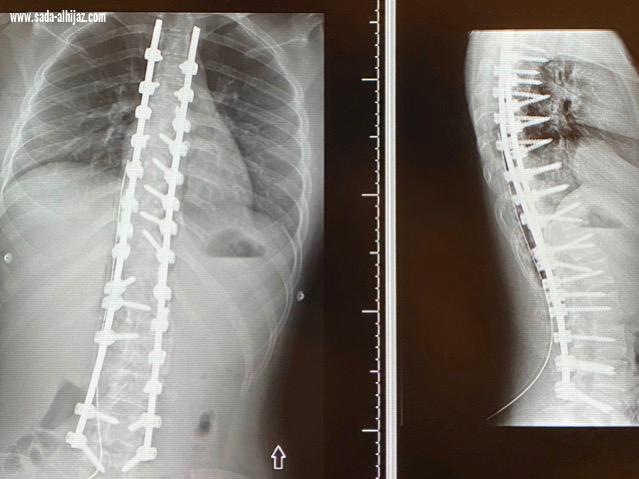

إنهاء معاناة مريضين من إنحناء للعمود الفقري في بيشة

بيشه .عيد البيشي تمكن بفضل الله المشرف العام على مستشفى الملك عبدالله ببيشة الدكتور صالح آل خبتي استشاري جراحة العظام وجراحة العمود الفقري إنهاء معناه مريضين من انحناء العمود الفقري بإجراء عمليتين جراحيه تكللت بالنجاح . الجدير بالذكر أن مستشفى الملك عبدالله في بيشة يعد واحد من الصروح الطبية على مستوى المنطقة، وهو مستشفى مرجعي وتبلغ سعته السريرية ٣٦٥ سرير، ويضم جميع التخصصات والأقسام الطبية المختلفة.